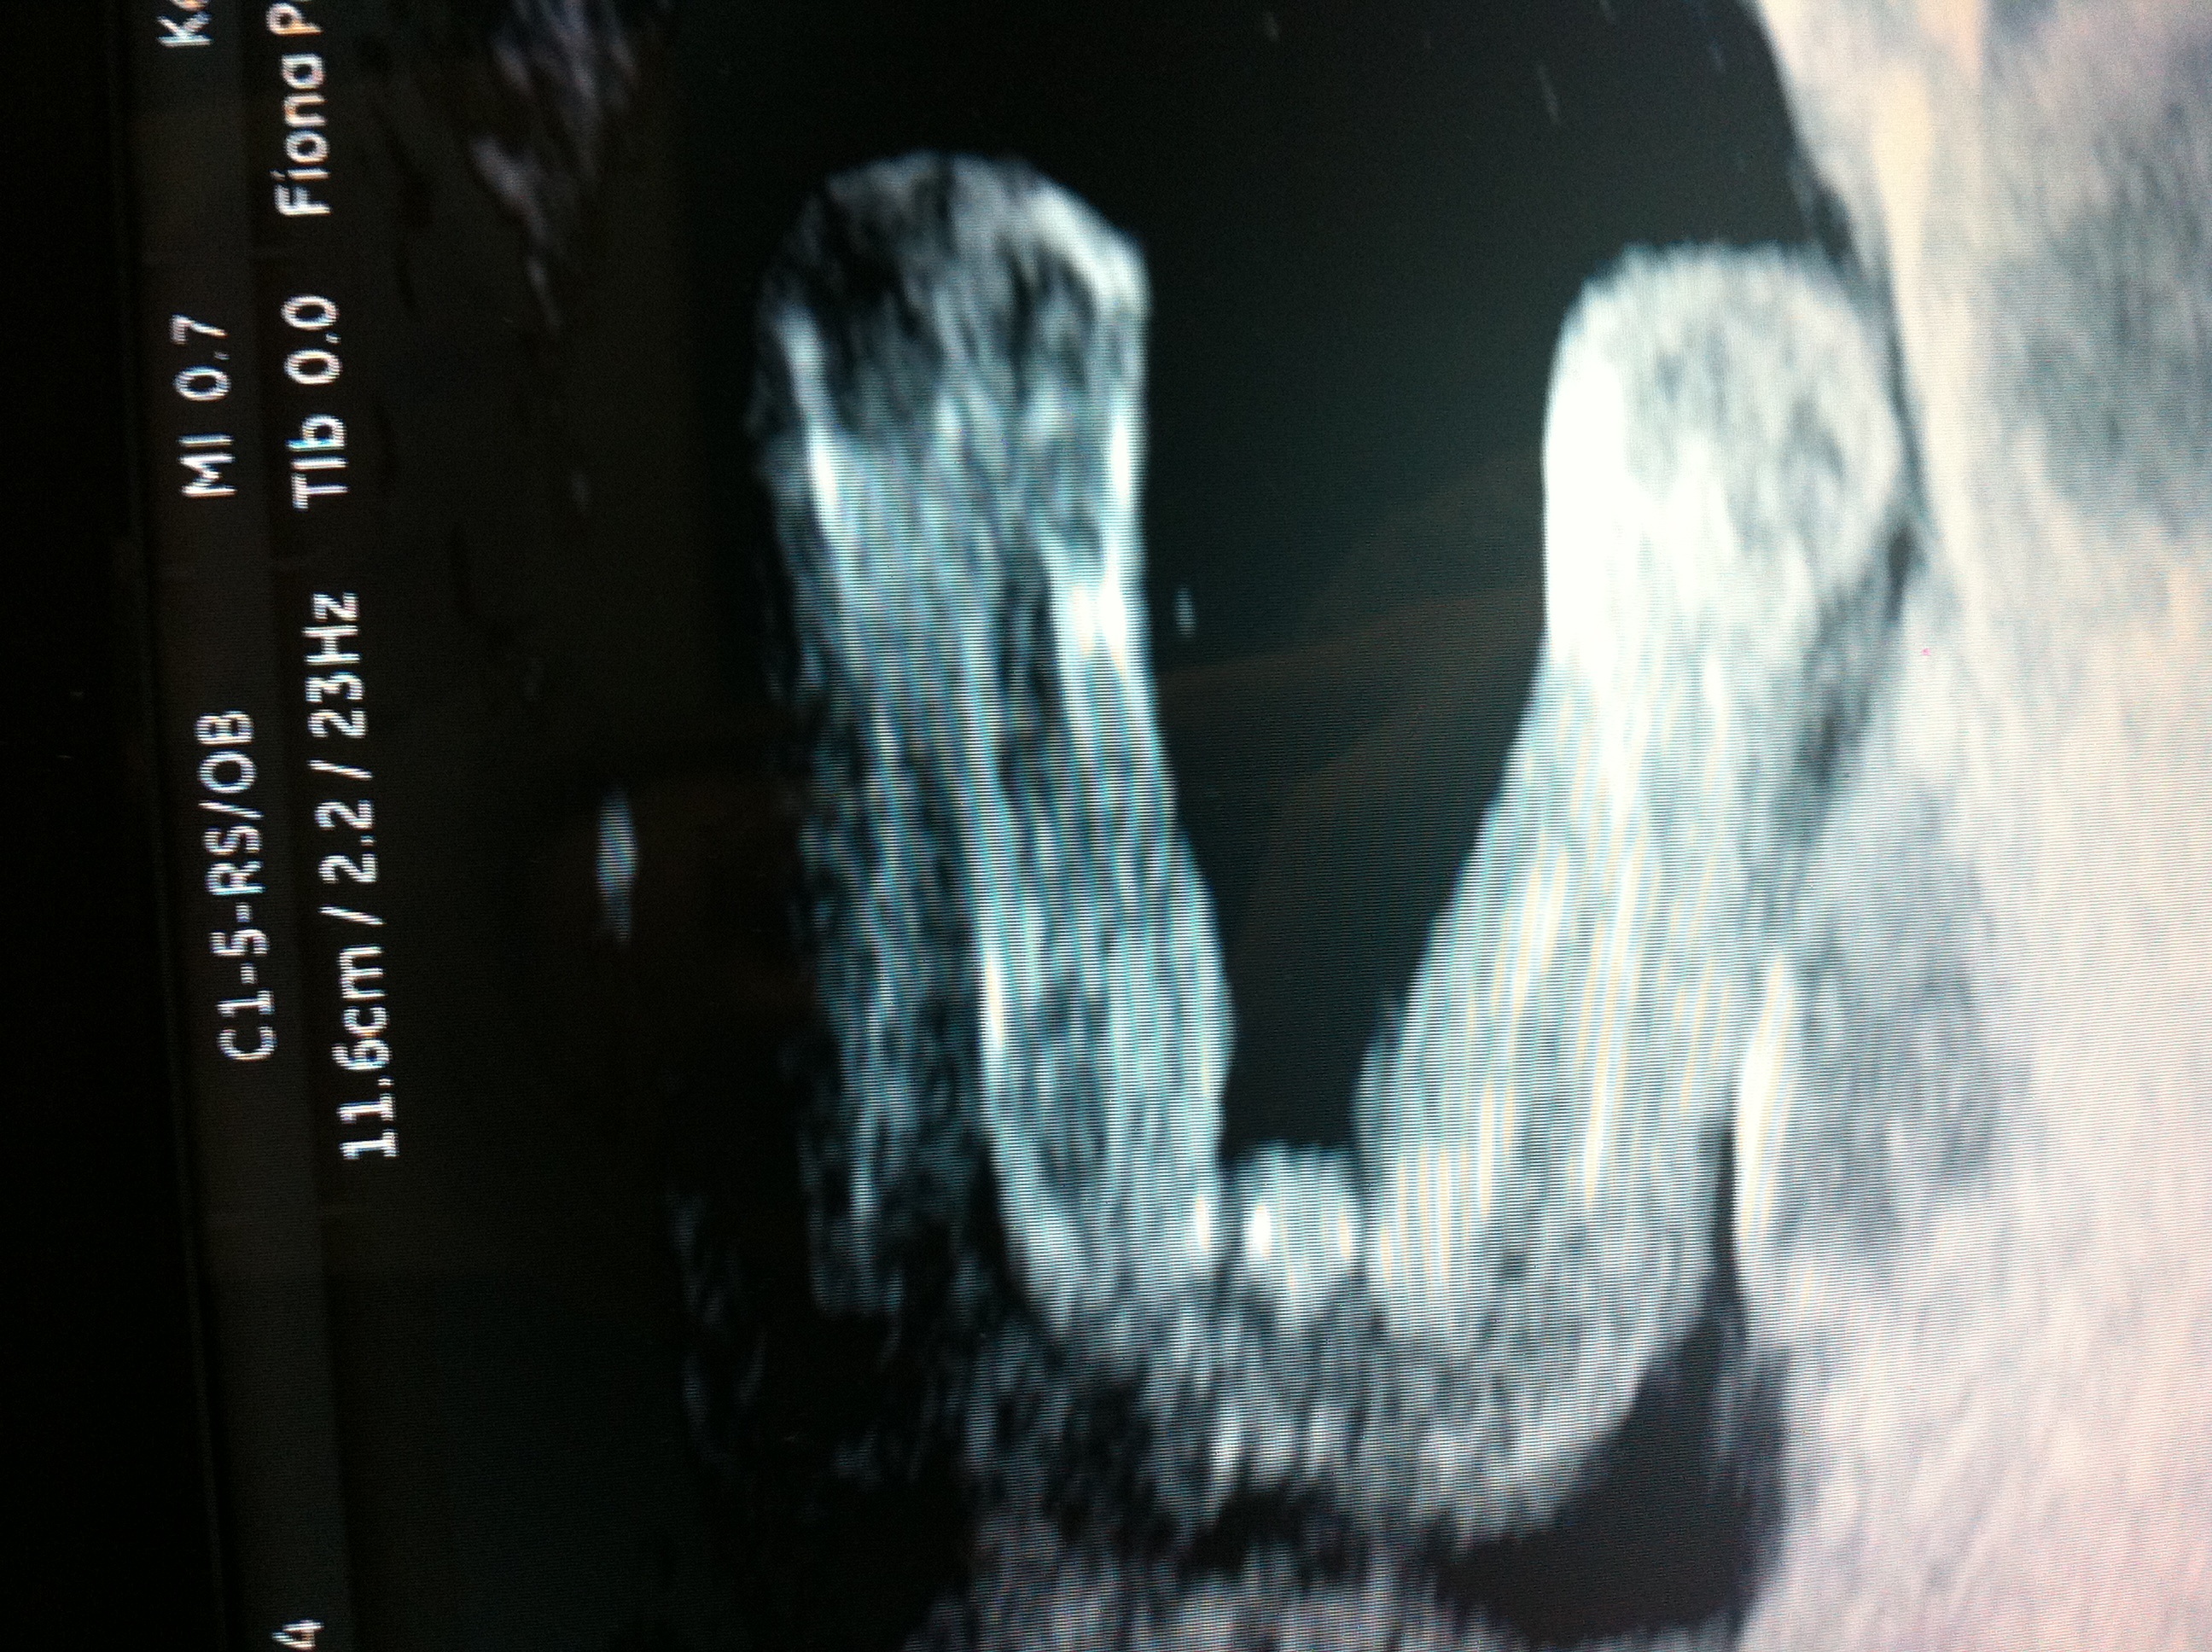

That's a girl :)

Girl

Girl!!!

I think girl.

Oh yes that's a Girl, Congratulations!